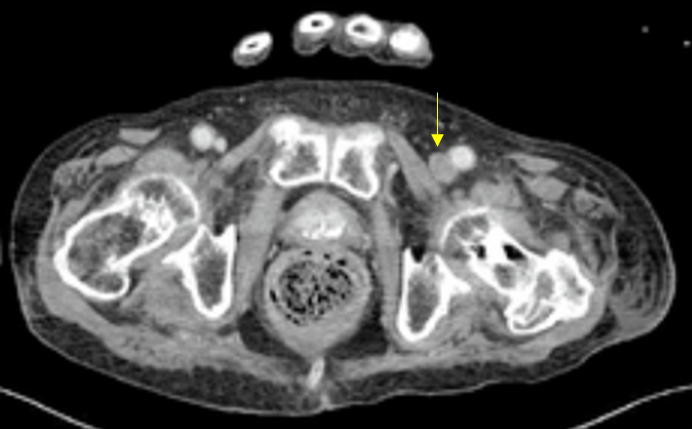

Img | CXR: 정상 CT: Lt. common iliac v. thrombus |

• 실제로 APCT에서 왼쪽 다리에 정맥 혈전이 발견된다(오른쪽 정맥에 비해 low attenuation을 보이며 팽창해있다).